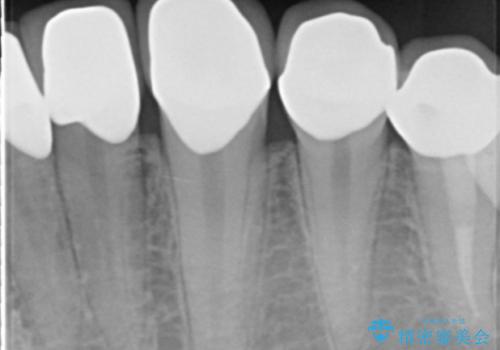

精査したところ、ほとんどの歯が保険内のレジンで充填されており、咬み合わせも悪く咬合していない歯もありました。

虫歯をしっかりと治療したのち、オールセラミッククラウンによる補綴治療を行いました。